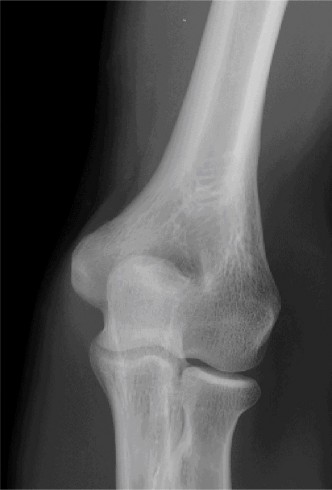

It should be noted that reverse total shoulder arthroplasty is also the procedure of choice in patients with cuff-tear arthropathy (aka rotator cuff arthropathy). Characteristics of cuff-tear arthropathy include superior migration of the humerus due to a massive rotator cuff tear, glenohumeral joint destruction, subchondral osteoporosis, and humeral head collapse (see Fig. 2–17). A reverse total shoulder

Figure 2–17_X-rays of a patient showing evidence of cuff tear arthropathy. The humerus is migrated superiorly, the glenohumeral joint is destroyed, there is subchondral osteoporosis, and the humeral head is collapsed. (From Ecklund KJ, Lee TQ, Tibone J, Gupta R. Rotator cuff tear arthropathy. _J Am Acad Orthop Surg. 2007;15(6):340–349.)